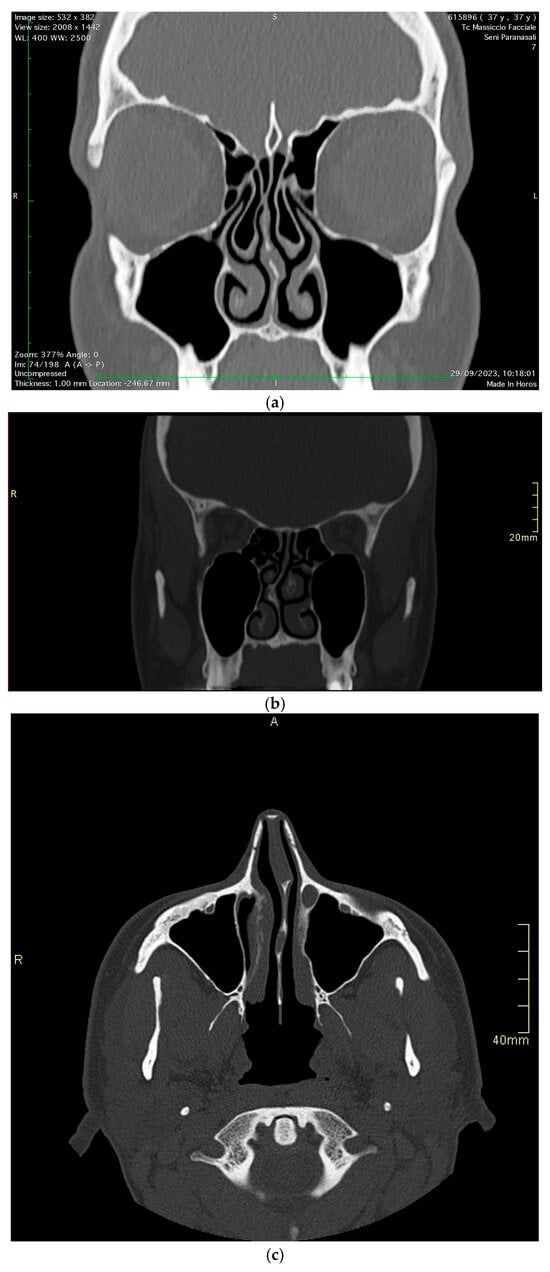

The study encompassed a patient pool from January 2021 to June 2024, consisting of 90 patients with chronic headaches attributed to nasal structural anomalies (Figure 2a–c).

Figure 2.

Different nasal structure anomalies. (a) Concha bullosa, (b) septal spur, (c) septal deviation.